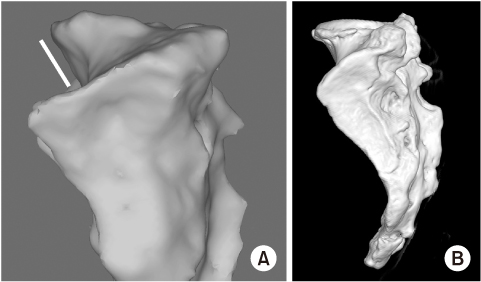

Fig. 1

(A, B) Sacral dysmorphism represents the acute angulation of sacral ala and reduced the corridor for iliosacral screw fixation. *Cortical perforation of screw.